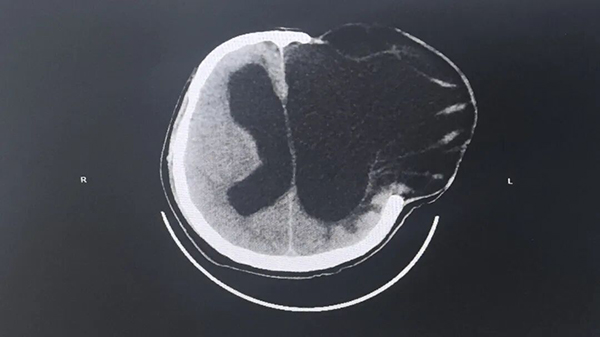

为寻求进一步诊治,家属带着李先生来到南通六院。接诊后,神经外科(二)团队详细询问病史,结合体格检查和影像学检查,对李先生的病情展开了细致评估,经诊断李先生为颅脑术后交通性脑积水,脑室扩张。

▲术前头颅CT影像